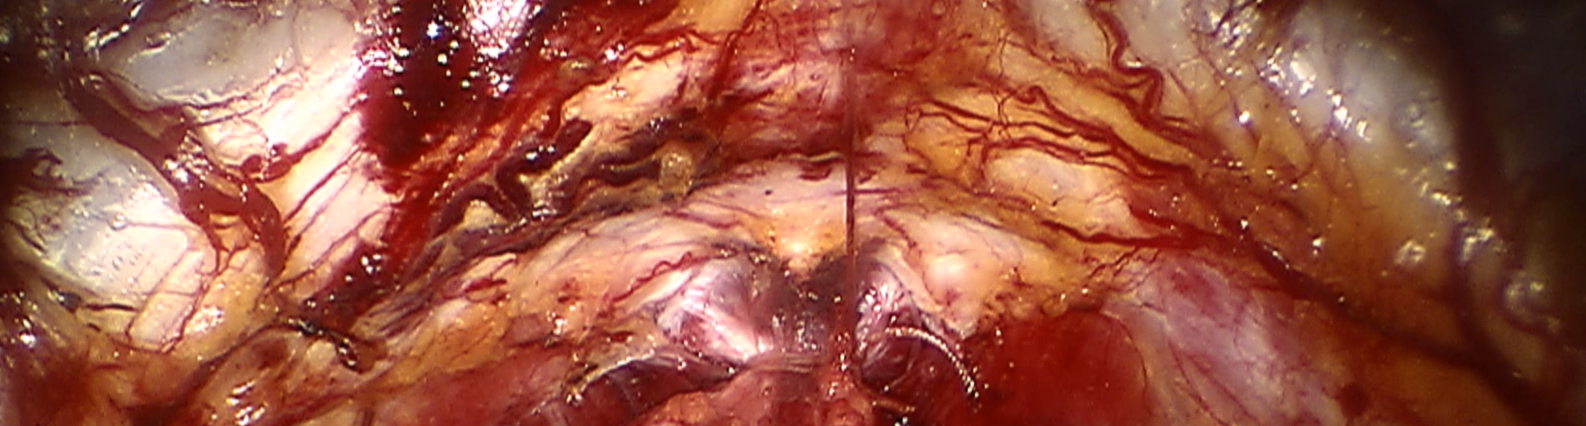

Refer to caption Refer to caption Refer to caption Refer to caption Refer to caption Refer to caption Refer to caption Refer to caption Refer to caption

Refer to caption (a) Input Refer to caption (b) DIACMPN Refer to caption (c) Desmoke-LAP Refer to caption (d) PFAN Refer to caption (e) MITNET Refer to caption (f) Salazar Refer to caption (g) Dehamer Refer to caption (h) Ours Refer to caption (i) Target

Figure 3: Comparison of different methods on the LSD3K dataset.

IV-C2 Qualitative Analysis

Figures 3 and 2 provide a visual comparison of the desmoking results on challenging images from the test sets. The visual results corroborate our quantitative findings. DCP not only fails to remove the dense smoke but also introduces severe color distortion. CNN-based methods like FFA-Net and MSBDN successfully remove a large portion of the smoke but tend to either leave behind a thin layer of residual haze or over-smooth the image, losing critical textural details of the tissue and surgical instruments. The Transformer-based methods, DehazeFormer and PFAN, produce significantly better results by restoring more details. However, they can sometimes struggle with non-uniform smoke distribution, resulting in regions with unnatural brightness or minor artifacts.

In stark contrast, our RGA-Net generates visually superior results that are remarkably close to the ground-truth images. It effectively removes even the densest plumes of smoke while simultaneously preserving fine-grained details, such as blood vessels, tissue textures, and reflections on surgical tools. Furthermore, the color and illumination of the restored scene appear more natural and consistent, which is a direct benefit of our model’s ability to handle both local and global features through its hybrid attention and cross-gating mechanisms. This enhanced visual clarity is crucial for improving the surgeon-robot interface in real-world clinical applications.